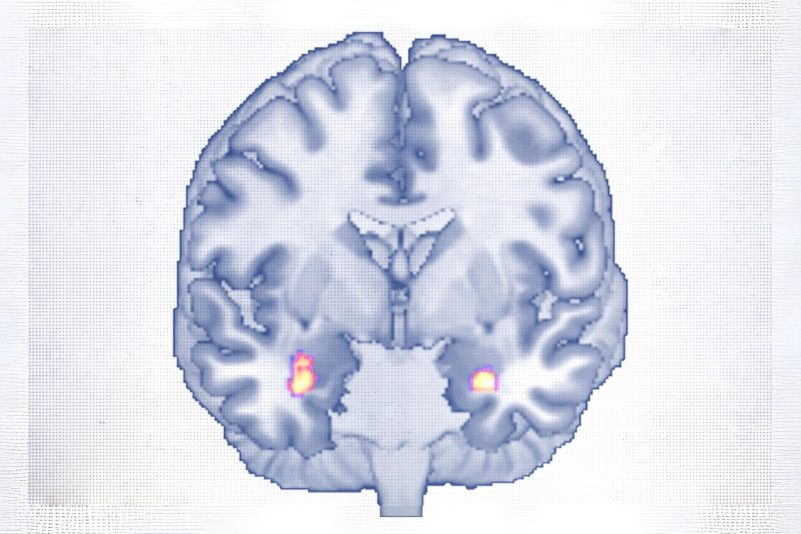

Modifications du volume de matière grise dans l'amygdale après une thérapie cognitivo-comportementale. Zwiky et al., (Translational Psychiatry, 2025. CC BY 4.0.)

L’étude a suivi 30 adultes âgés de 18 à 65 ans souffrant d’un trouble dépressif majeur, ayant bénéficié d’environ 20 séances de TCC sur une période de 40 semaines. Des IRM à haute résolution réalisées avant et après le traitement ont montré une augmentation du volume de la matière grise dans l’amygdale — une zone clé du traitement émotionnel — et dans l’hippocampe antérieur, impliqué dans la mémoire et la régulation de l’humeur.

Ces deux régions sont connues pour se rétracter chez les personnes dépressives, et leur croissance pourrait donc indiquer un processus de guérison, ont souligné les chercheurs. À la fin de l’étude, 19 des 30 participants ne répondaient plus aux critères cliniques de la dépression.

L’augmentation de la matière grise dans l’amygdale était corrélée à une meilleure capacité à percevoir les émotions, notamment les siennes, précise le Pr Redlich.